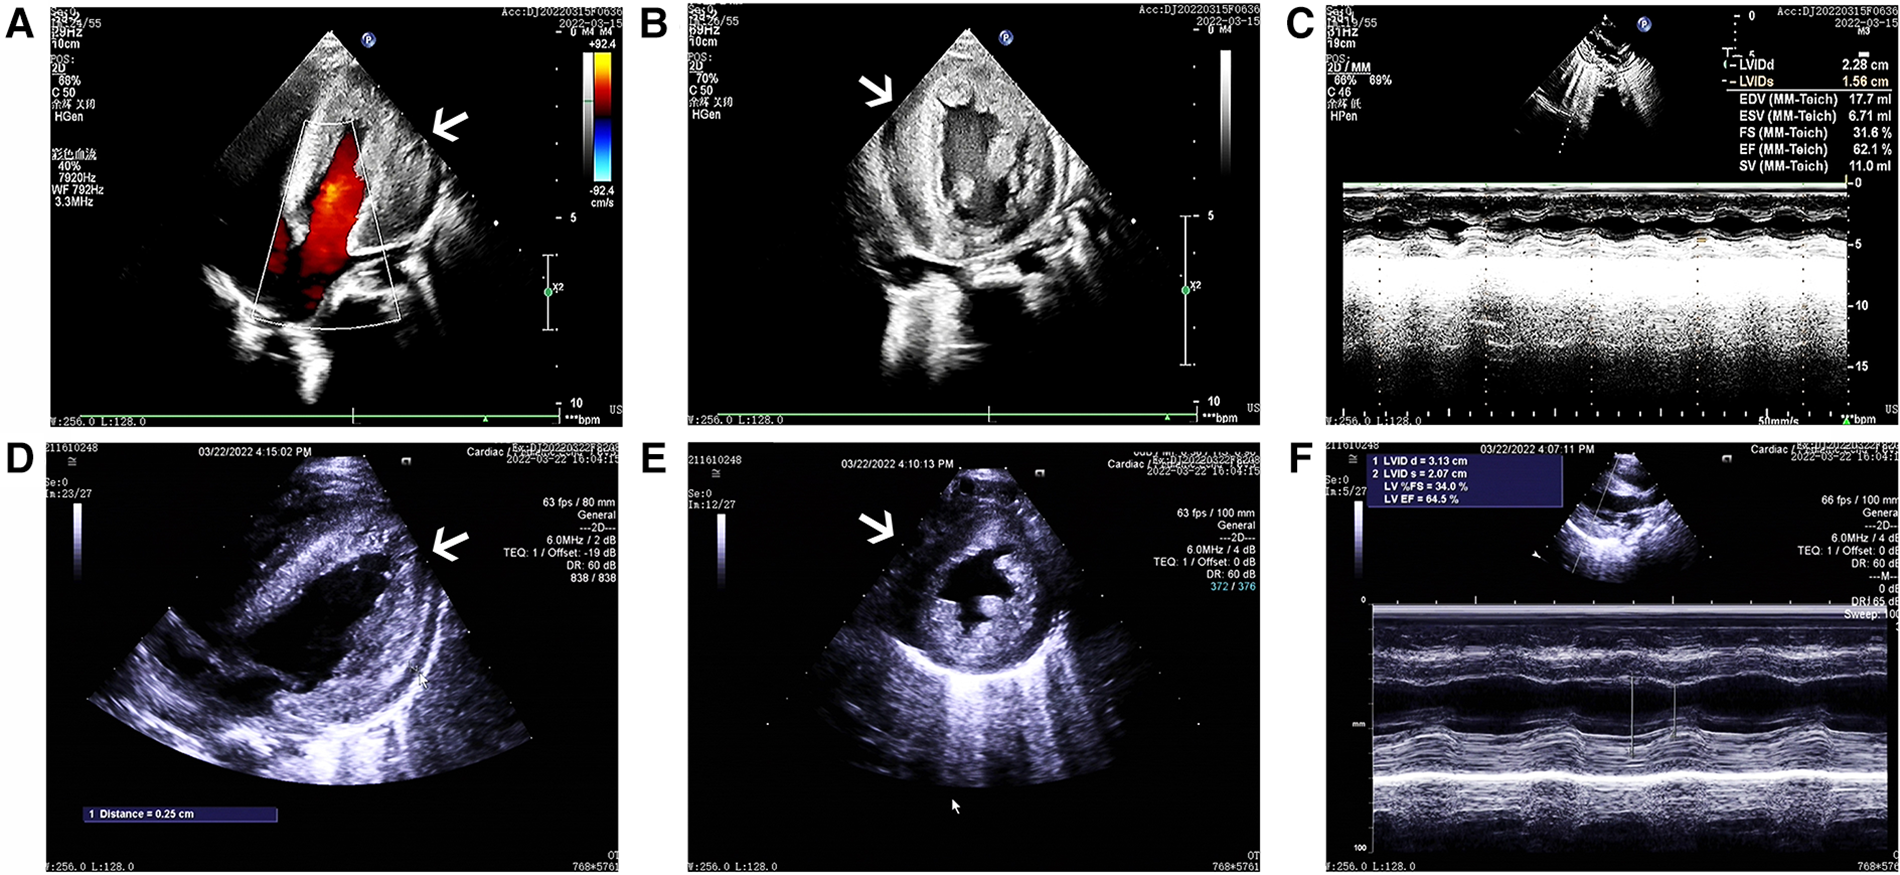

The cardiac echocardiography (Figures 1A–C) showed diffuse thickening of the left ventricular wall, with the anterior wall approximately 9.5 mm thick, the interventricular septum around 8 mm, the lateral wall about 9 mm, and the inferoposterior wall approximately 9 mm. The thickened myocardial wall had increased echogenicity and stiffness, with generally reduced movement amplitude. The endocardium of the left ventricle was thickened, up to about 5 mm. The ejection fraction (EF) was 62%, and the shortening fraction of the left ventricular short axis (FS) was 31%. Color Doppler Flow Imaging (CDFI) showed no shunt at the ventricular level. A small left-to-right shunt was observed at the middle of the interatrial septum (foramen ovale), approximately 2 mm wide. A small amount of regurgitation was noted at the mitral valve, and a trace regurgitation signal was seen at the tricuspid valve with a regurgitation speed of 1.8 m/s, estimating pulmonary artery pressure at 18 mmHg (right atrial pressure assumed to be 5 mmHg). The abdominal ultrasound showed hepatomegaly and edematous gallbladder walls. The chest CT scan revealed normal translucency in both lungs with disordered patterns, patchy areas of increased density, localized consolidation with visible air bronchograms, normal hilar shadows, and clear airways. The cardiac silhouette was enlarged, with thickening of the left ventricular myocardial wall (Figure 2A). The electrocardiogram showed sinus tachycardia, enlargement of the left atrium and left ventricle, accompanied by ST-T changes (Figure 3).

Figure 1

The ultrasound echocardiograms of the patient showed significant myocardial hypertrophy. The images (A–C) sequentially represent the apical four-chamber view, the left ventricular short-axis view, and the M-mode ultrasound changes before treatment. Similarly, images (D–F) represent the same views and changes after treatment.

After one week of regular anti-infection treatment, liver protection, and heart function improvement, the infant's body temperature normalized, and a recheck showed a significant decrease in N-terminal pro-brain natriuretic peptide (1,730.94 pg/ml). CT scans indicated reduced lung inflammation (Figure 2B). However, a follow-up cardiac echocardiography (Figures 1D–F) still indicated symmetric hypertrophic cardiomyopathy (non-obstructive type) with thickening of the left ventricular endocardium, and decreased left ventricular systolic and diastolic function (EF 48%, FS 22%). The liver size had not noticeably reduced, and there was no improvement in the liver function tests (alanine aminotransferase and aspartate aminotransferase) compared to admission. Serum creatine kinase levels were 476 U/L, which was inconsistent with clinical expectations. This lack of noticeable improvement in the echocardiographic images underscores the severity and progression of the disease, despite the treatment efforts.